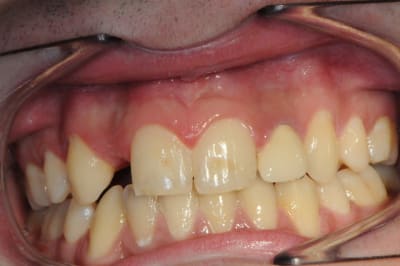

jeune homme,

18 ans,

agénésie de 12,

extraction de 52 depuis 2 ans et remplacement par un mainteneur d'espace, vient consulter pour un implant...

j'adore ce genre de cas, c'est un vrai défi esthétique où on a pas le droit à l'erreur.

je pense qu'une greffe osseuse serait peut être nécessaire pour la concavité. Toutefois, je devrais pouvoir m'en sortir en dilatant la crête osseuse vestibulaire pendant la pose de l'implant.

Tu peux aussi aider avec la 22, pas très jolie.